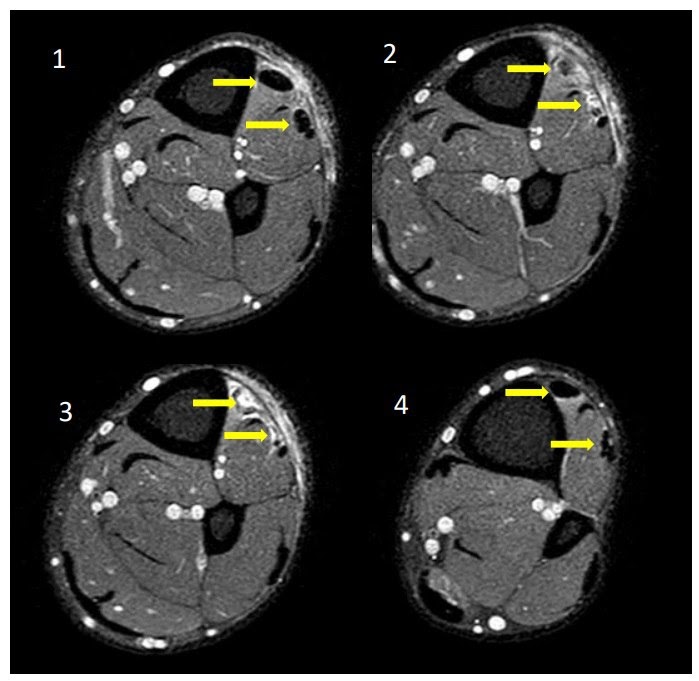

И опять у невролога возникли сомнения относительно верности интерпретации исследования, в связи с чем врач обратился к врачу МРТ с диском. И опять не зря! По снимкам выявлено выраженное повреждение сухожилий передней большеберцовой и длинной малоберцовой мышц, что и прояснило причину нарушения движений в левой стопе. На рисунке стрелками указаны поврежденные сухожилия — вначале целые, потом разрыв, затем вновь нормальная структура.